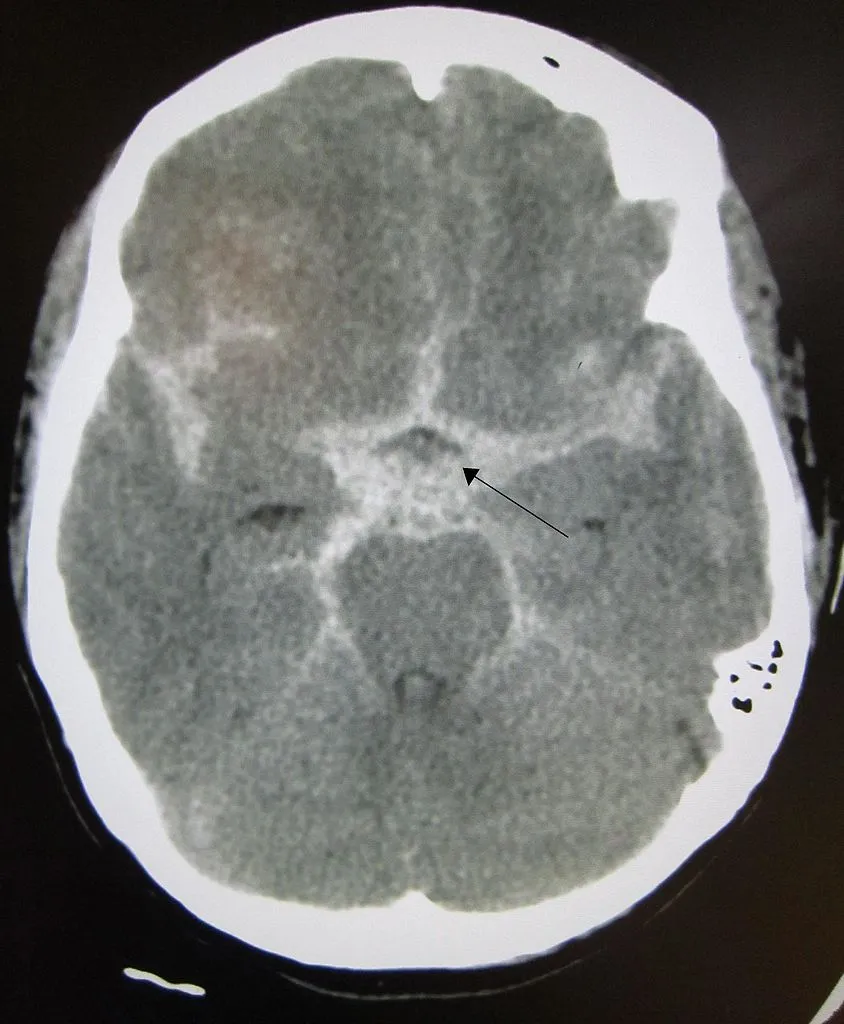

normal brain.jpg

844px-SAH1.JPG

화질이 조금 떨어지지만 좌측이 정상 뇌 CT 사진이고 우측이 지주막하 뇌출혈이 발생한 사진이다. 하얗게 보이는 부분이 (화살표) 출혈이 있는 부분으로 뇌 전반에 퍼져 있는 것이 관찰된다.